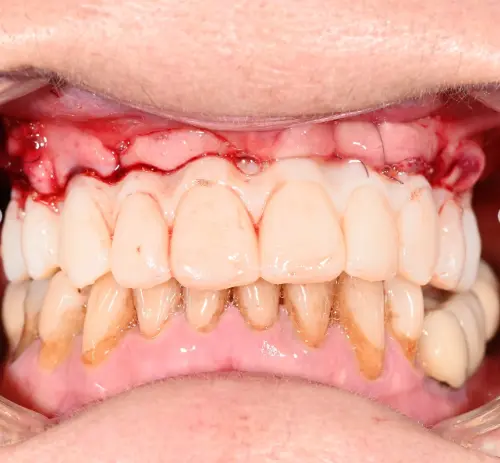

Dysfonction occlusale et esthétique avec inflammation gingivale, usure dentaire marquée et axes implantaires défavorables au maxillaire, compromettant une réhabilitation prothétique transvissée sans correction d’angulation.